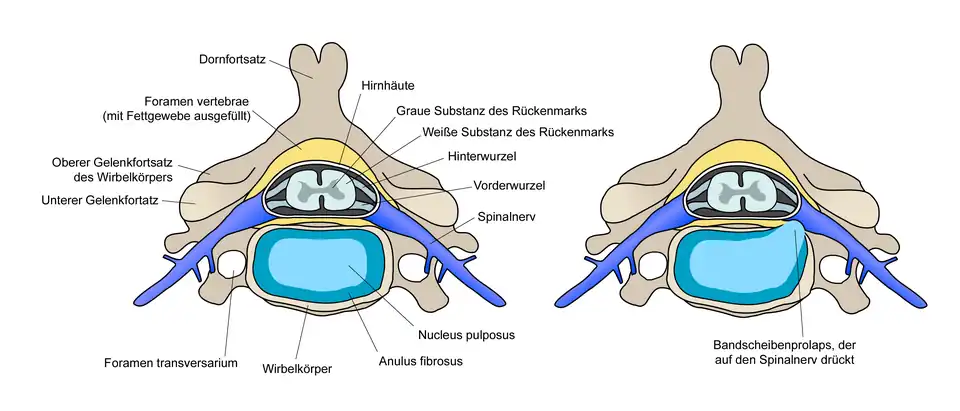

Der Bandscheibenvorfall (lateinisch Prolapsus nuclei pulposi, ärztlich oft Nucleus-pulposus-Prolaps, kurz NPP), auch Bandscheibenprolaps (BSP), Bandscheibenhernie, Discushernie (oder Diskushernie) und Discusprolaps, ist eine Erkrankung der Wirbelsäule, bei der Teile der Bandscheibe in den Wirbelkanal – den Raum, in dem das Rückenmark liegt – vortreten. Im Gegensatz zur Bandscheibenprotrusion (Vorwölbung) wird beim Prolaps der Faserknorpelring der Bandscheibe (Anulus fibrosus) ganz oder teilweise durchgerissen, während das hintere Längsband (Ligamentum longitudinale posterius) intakt bleiben kann (sogenannter subligamentärer Bandscheibenvorfall).

Bandscheiben sind bradytrophe Gewebe, das heißt, sie werden nicht direkt aus dem Blutkreislauf heraus mit Nährstoffen versorgt, sondern durch Diffusion. Hierbei spielen semipermeable Membranen, welche die Knorpelringe voneinander trennen, die entscheidende Rolle. Durch Scherkräfte können diese Membranen einreißen, wodurch sie ihre Funktion verlieren und die Bandscheibe nebst Gallertkern der Bandscheibe (Nucleus pulposus) austrocknet (black disc lesion). Wenn es zu einem Bandscheibenvorfall kommt, ist der Gallertkern praktisch nicht mehr in seiner ursprünglichen Form vorhanden. Der Bandscheibenvorfall entsteht also zumeist auf dem Boden einer langjährigen Vorschädigung der Bandscheibe. Der Gallertkern (ca. 80 % Wasser) besteht bei der gesunden Bandscheibe aus einem gallertigen, zellarmen Gewebe und übernimmt bei Belastung zusammen mit den Knorpelringen und den Membranen die Funktion einer hydraulischen Kugel („Wasserkissen“). Die Wirbelkörper und Bandscheiben vorne ermöglichen zusammen mit den kleinen Wirbelgelenken hinten („Facettengelenke“) die hohe Beweglichkeit der gesamten Wirbelsäule und ihre hohe Stabilität.

Typischerweise verursachen Bandscheibenvorfälle Rückenschmerzen (Lumbalgie) mit oder ohne Ausstrahlung in die Beine (Ischialgie) oder in die Arme (Brachialgie). Bei der mediolateralen Diskushernie werden tiefliegende Nerven komprimiert. Je nach Schwere der Symptomatik kann es dann auch zu einem Taubheitsgefühl oder zu einem Muskelausfall im Versorgungsgebiet der eingeklemmten Nervenwurzel kommen.[8]

- Bandscheibenvorwölbung (Bandscheibengewebe ist lediglich nach außen vorgewölbt, der Anulus fibrosus (Faserring) ist intakt)